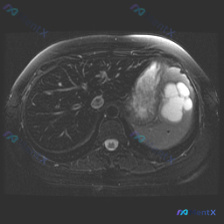

今天看到一份腹部MRI的T2WI图像,焦点在脾脏,整理一下读片的思考过程,避免踩坑。 先看核心影像表现 这是一张轴位T2WI,最突出的异常在脾脏: - 信号:脾实质内有数个类圆形极高信号影,信号强度接近脑脊液,提示是液体(浆液性为主)。 - 形态:边界清晰,但边缘呈分叶状,囊腔之间相互融合或紧邻,不...

整理了一份腹部囊性病变的影像资料,结合影像分析报告梳理下思路: 影像核心表现(T2加权轴位) - 肝脏:信号无明显弥漫或局灶异常 - 脾脏:可见类圆形多房性囊性病灶,边界清晰,T2呈显著高信号(符合囊液信号),无周围浸润或水肿带 - 上腹部额外发现:胰腺体尾部前方/胃后方,还有一个孤立的、边界清晰的...